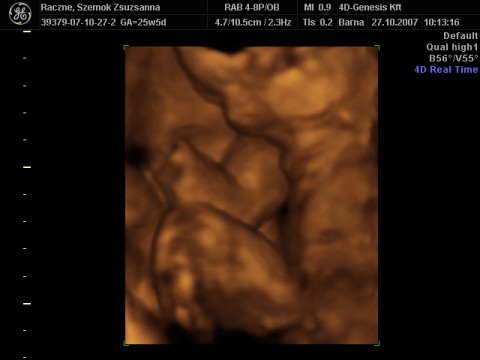

Zsu,

még jó , hogy jók lesznek a képek.

Remélem jobban látszik az én kis szerelmem!!!!